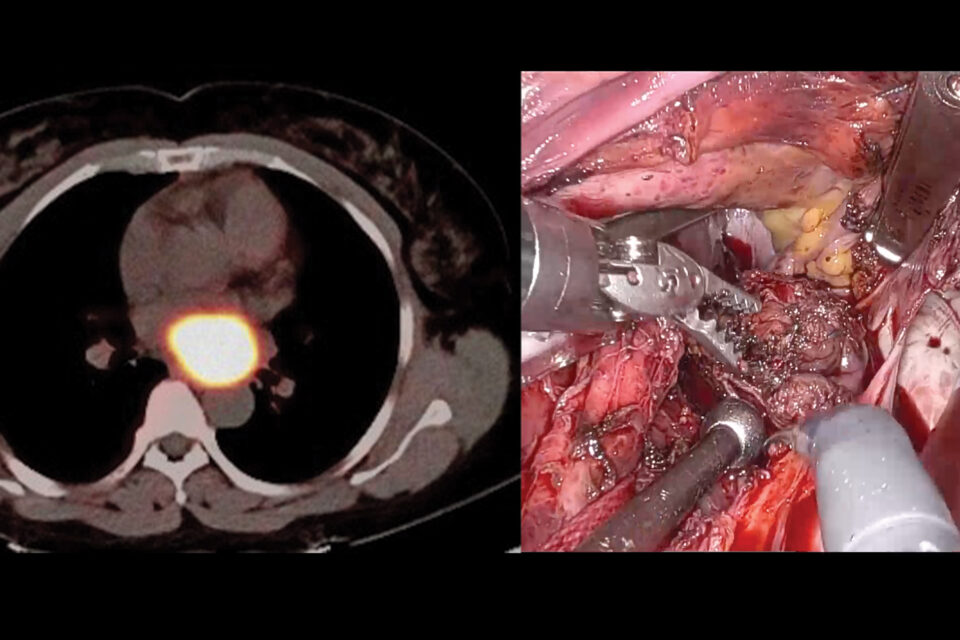

Dr. Harmony G. Reynolds and a research team are proving that OCT and cardiac MRI and can clarify why many women have heart attacks without coronary artery narrowing. Read the interview.